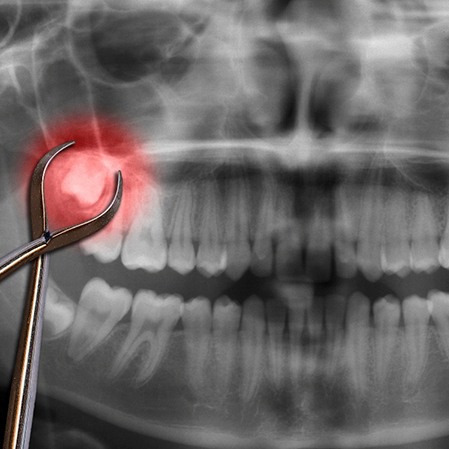

There are two ways to remove wisdom teeth: simply or surgically. If the molar has partially erupted and is slightly visible above the gumline, your dentist in San Antonio can use a dental elevator and dental forceps to lift the tooth from its socket and gently move it back and forth until it detaches.

If the molar remains below the gumline, it is deemed impacted. This requires opening the gum tissue and exposing the underlying tooth and bone. Removing it slowly and with careful precision ensures minimal damage to the bone.